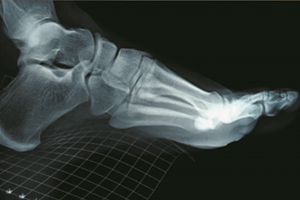

Al tomar los patrones de movimiento, se puede determinar la base de sustentación del cuerpo, que incluye los pies, tobillos, rodillas y cadera. Importante para saber si un corredor, aficionado o profesional, necesita plantillas de respaldo que le permitan evitar lesiones en las articulaciones. Es importante el tema preventivo, evitar los dolores crónicos de espalda con una simple evaluación ortopédica de pie.

Ronald Contreras, un médico fisiatra con especialidad en biomecánica, propone una innovadora tecnología desarrollada por su equipo de trabajo. Se trata del BioDinamic Sport, un aparato que toma las medidas de las plantas del pie, cuando la persona está de pie, en marcha o corriendo, la finalidad es determinar el tipo de plantillas que necesita, según la actividad que realiza. Esta tecnología puede implementar principios de telemedicina, que es brindar asistencia médica a distancia, incluso al punto de que las tiendas de zapatos e implementos deportivos posean una estación de telemetría en sus instalaciones, en donde los clientes puedan incorporar las plantillas que son clínicamente correctas para ellos y sus actividades.